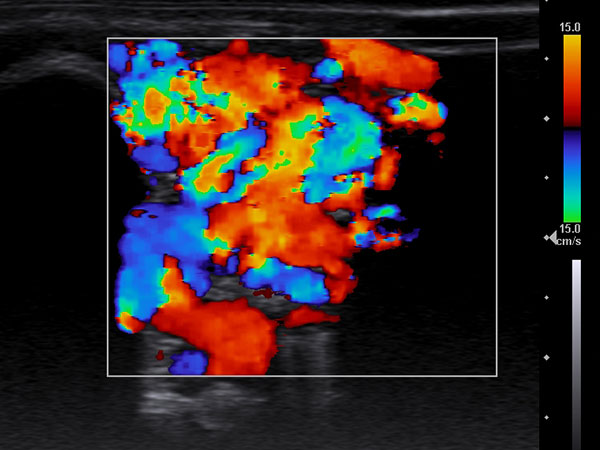

In der farbkodierten Duplexsonographie (FDKS) sieht man bereits bei einem mittleren Setting der Pulswiederholungsfrequenz eine massive Perfusion praktisch der gesamten, aus durchströmten Gefäßen bestehenden Läsion. Dies typisch für eine Fast-flow-Malformation, hier eine arteriovenöse Malformation.